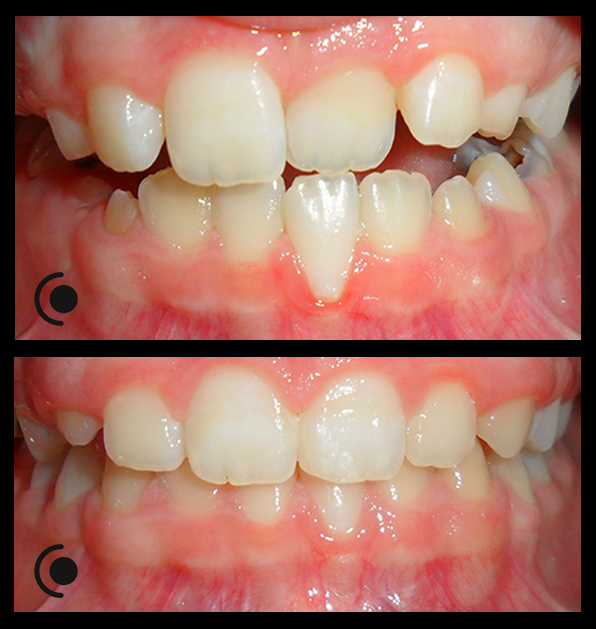

O našoj kvaliteti najbolje govore naši rezultati!

Centar za ortodonciju Petra Džapo